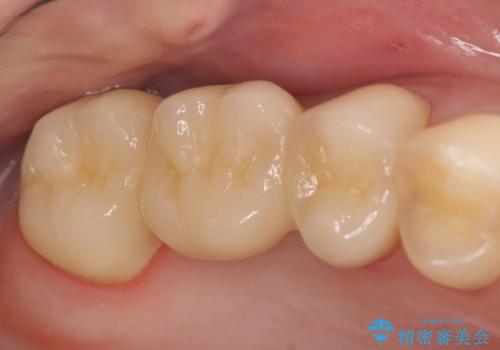

![[根管治療・セラミック補綴] 歯ぐきを押すと痛いの症例 治療後](https://seimitsushinbi.jp/wp/wp-content/uploads/2020/06/f06e35140e887def91fb23d77e0ff069-500x350.jpg?v=1591340046)

オールセラミッククラウン 奥歯のブリッジ